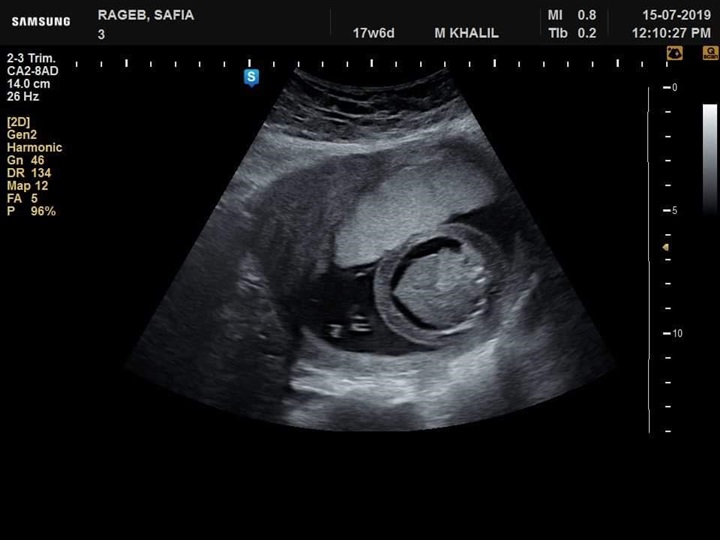

نجح فريق طبي من قسم النساء والتوليد في مستشفى جامعة كفر الشيخ في تشخيص  حالة تم تحويلها إلي مستشفي الجامعة بسبب وجود زيادة في السائل الامنيوسي، وبعد توقيع الكشف وتصوير للجنين تفصيليا تم اكتشاف وتشخيص جنين داخل رحم أمه وبه انسداد المرئ ووجود ناصور بين القصبة الهوائية والمرئ

عدم تكوين الجسم الثفني الذي يصل فصي المخ سويا وجود تشوه في القدم وابتعاد ألاصبع الكبير للقدم عن الإصبع الآخر وزيادة في السائل الامنيوسي تم بذل لتر و ٨٠٠ سم من السائل الأمنيوسي وإرسال بعضه للتحليل الكروموسومي.

وأوضح الفريق الطبي في قسم النساء والتوليد بمستشفى جامعة كفرالشيخ برئاسة الأستاذ الدكتور محمد خليل أنه تم تشخيص حالة أخري استسقاء لجنين داخل الرحم لأسباب جينية وحالة أخري بضمور كليتي الجنين وهذا التشخيص المبكر يساعد علي مساعدة الجنين الأول بعمل عملية له بعد الولادة لإصلاح الانسداد بالمرئ وإصلاح الناصور أما في الحالتين الثانيتين فينصح بعدم تعرض الأم لعمل عملية قيصرية في مثل هذه الحالات.